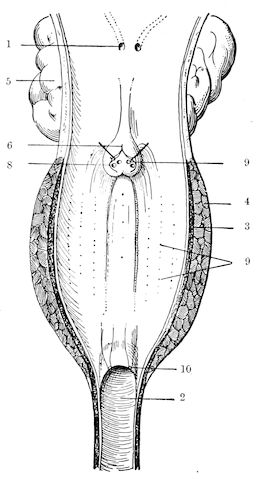

Fig. 1.—Rachitis in a young goat.

Rachitis is a disease of youth, and is common both to the human species and to all domestic animals. It is characterised by irregularities in development and by imperfect consolidation of the bones. The boundary between rachitis and osseous cachexia is difficult to define and in fact at the present moment the two diseases can scarcely be defined with exactitude. Rachitis again is often complicated with softening of the bones, disease of the limbs, arrested development, etc., but it must not be forgotten that although the irregularities in ossification and development of the skeleton are the symptoms most striking to the eye, they do not stand alone, and that from the point of view of development all the tissues, including the muscles, are more or less affected and that most of the physiological functions such as digestion and the secretion of urine are deranged.

Symptoms. The onset is absolutely insidious and the diagnosis of rachitis is never made until nutrition has long been abnormal.

This disturbance of nutrition is revealed by irregularity and abnormality in appetite, by difficulty in rising and moving about, and by the animals lying down for long periods. The subjects are feeble, sluggish and badly developed.

Next supervenes the second phase characterised by deformity of bones. This is of two kinds—deformity in the neighbourhood of joints (deformity or enlargement of the epiphyses) and deformity of the diaphyses. The former results from irregularity in ossification of the articular cartilages. The latter is followed by loss of rigidity in the bones of the limbs which, under the influence of the body weight and of muscular contraction, bend in different directions.

The bones appear of increased thickness principally towards the 6articulations. The latter are deformed, and on palpation are found to be surrounded by uneven and irregular growths.

The front limbs are distorted. In young pigs, lambs, and less frequently in foals, calves and dogs, the jaws become deformed, and mastication is rendered difficult.

The vertebral column may also be affected, and lordosis (bending downwards of the back) or skoliosis (lateral bending of the back) is somewhat frequent.

Cyphosis, or upward bending of the back, seldom occurs, and when seen, sometimes results from disease other than rachitis.

General development is always interfered with and the young creatures are generally dwarfed.

The digestive apparatus is disordered, the appetite is irregular and sometimes depraved, while indigestion, gastritis, and enteritis are not exceptional. Physiological and pathological research has shown that the quantity of phosphoric acid eliminated in twenty-four hours in a rachitic child is double the quantity passed by a healthy infant. The amount of urea in the urine (which is a criterion of nutrition, and usually varies in proportion to the amount of food ingested) is, on the contrary, diminished even when highly nitrogenous food is given, thus suggesting diminution in nutrition.

Lesions. The lesions are represented by abnormal and irregular thickening around the interarticular cartilages. The cartilage is thickened, compressible, very spongy and without regular ossification. Diffused periostitis exists principally towards the extremities of the bone. Beneath the periosteum the surface of the bone appears rough and softened. On section the medullary canals are seen to be enlarged and filled with marrow of a gelatinous character. The Haversian canals are dilated, and the entire tissue appears very vascular. Chemical analysis proves that the mineral constituents of the bone, particularly the phosphates, have diminished by one-half; the organic constituents on the other hand are increased in a similar ratio, but the ossein is abnormal. Ossification has, in a word, been incomplete.

7Diagnosis. Diagnosis presents no difficulty except in the early stages before deformity has occurred.

Rachitis can scarcely be mistaken for any other condition except perhaps infectious rheumatism, but the rapid course of the disease in the latter case, the persistence of fever and the swelling of the joint cavities sufficiently differentiate the conditions provided care is exercised.

Prognosis. From an economic point of view the prognosis is very grave for if the lesions are extensive there is nothing to be gained by keeping the animal.

Treatment. Treatment differs very little, whether the animals are still being suckled or have been weaned. In the former case it is necessary to improve the quality and chemical constitution of the mother’s milk by giving food, richer both in mineral salts and in nitrogenous material.

Cooked grains, milk, and forage of good quality should be given freely. When the mothers are exhausted and anæmic it is better to feed the little animals artificially or to change them to a foster-mother. Those already weaned should be given good rich milk, eggs, boiled gruel, and drugs, such as the phospho-chlorate of lime, 1 to 1½ drachms per day (for a calf); lacto-phosphate of lime, 1 to 1½ drachms; bi-phosphate of lime, 1 drachm, or simply ordinary phosphate of lime. Oil containing 1 per cent. of dissolved phosphorus may be given in doses of 1 to 2½ drachms, according to the size of the calves, but its use calls for much care, and it should only be given for alternate periods of a fortnight. The glycerophosphates are not very active. Beef meal in doses of 6 drachms to 1½ ounces and chloride of ammonium in doses of 30 to 60 grains have also been used advantageously. The above drugs, but particularly the bi-phosphate of lime and chloride of ammonium, stimulate nutrition and diminish the quantity of phosphoric acid eliminated.